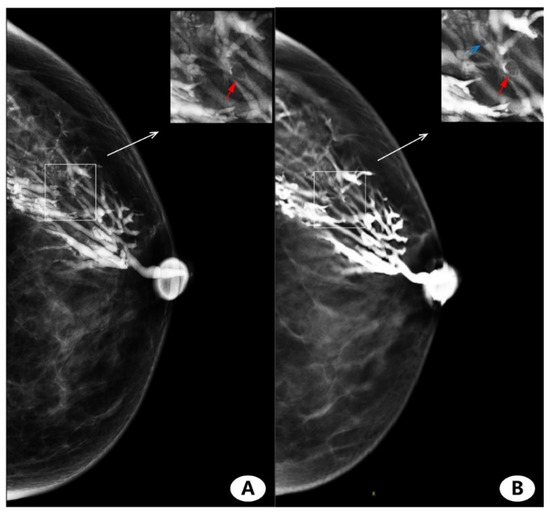

3.3. Visual Image Analysis

3.4. Imaging Finding